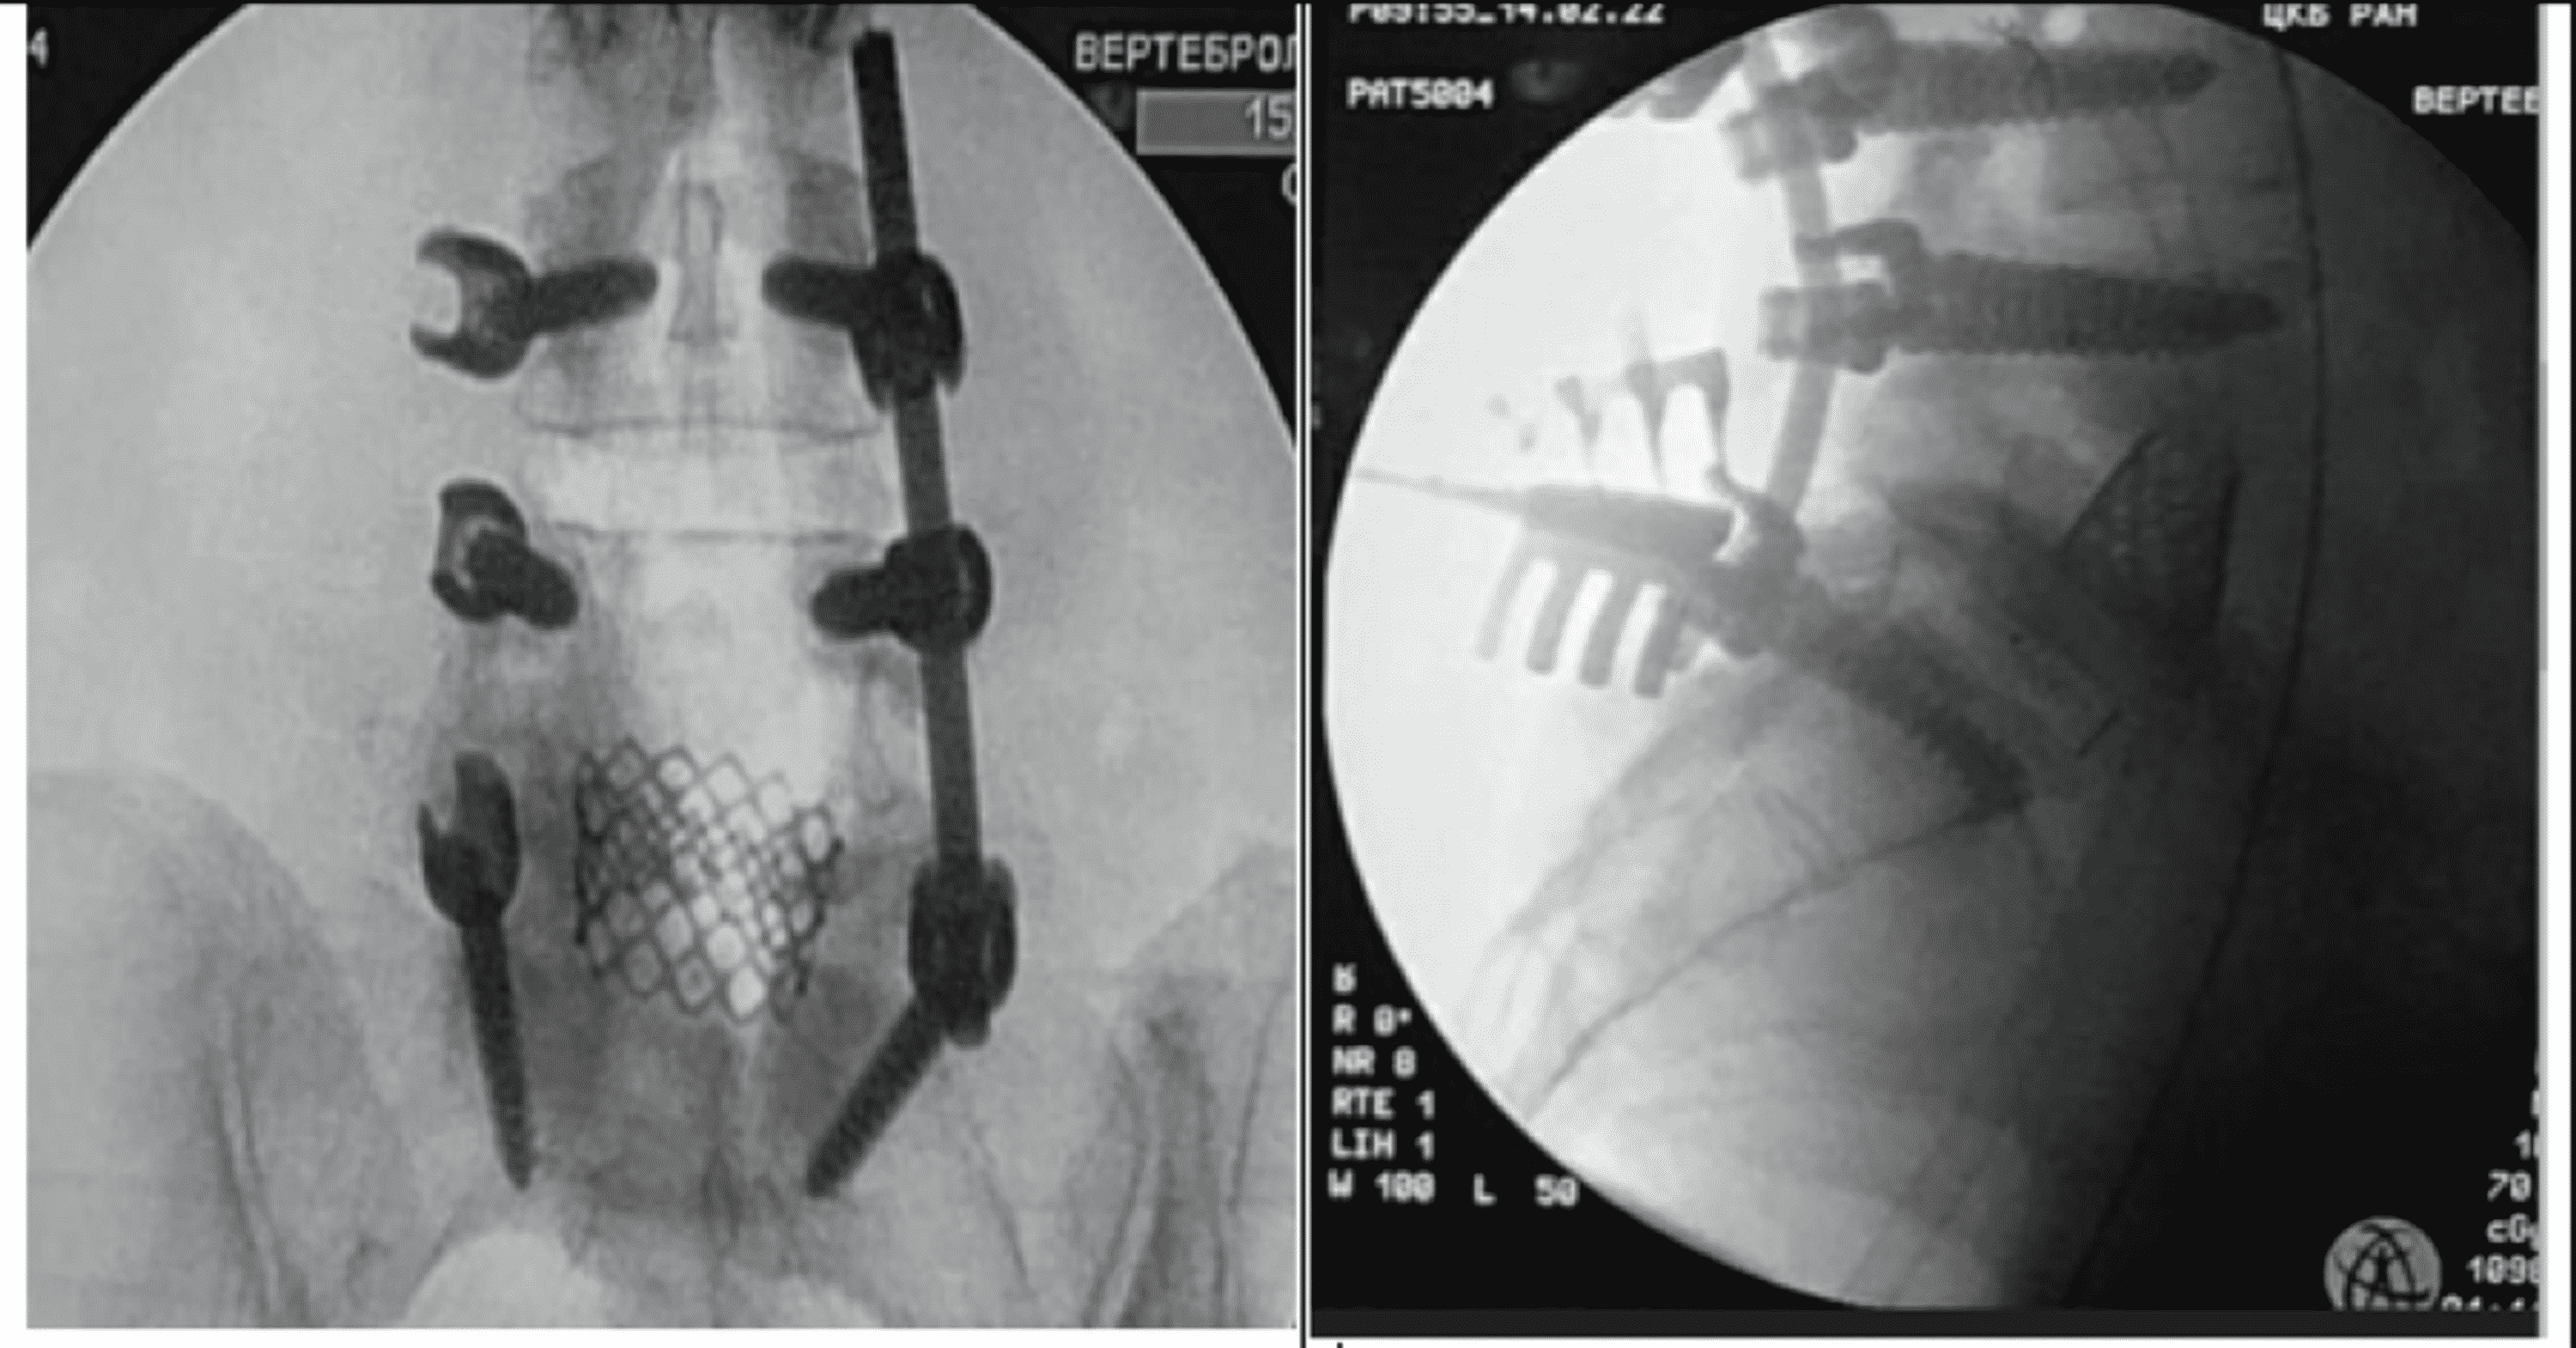

Spinal fusionhardware construct Basic concepts and imaging review

Spinal fusionhardware construct Basic concepts and imaging review Spinal Fusion Hardware Failure Icd 10 This article explains the key elements of spinal fusion. Learn how to code removal of hardware from a previous spinal fusion in addition to the new fusion (if performed) at the same level. This code is for other mechanical complication of internal fixation device of vertebrae, such as loosening of hardware in spine. Learn about the causes, symptoms and treatment. Spinal Fusion Hardware Failure Icd 10.